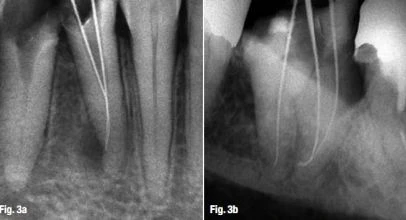

Thực tế là lỗ chóp giải phẫu không nằm ở vùng chóp giải phẫu,và cũng ko nằm ở vùng chóp trên X-quang. Do đó, các dụng cụ đặt vào ống tủy chân răng đi ra lỗ chóp với các góc khác nhau từ 10o đến 90o  (Hình 3a & b). Nói cách khác, các ống tủy chân răng lệch và đi ra ở phía gần và xa, điều này có thể dễ dàng thấy được trên phim X-quang. Tuy nhiên, ống tủy cũng lệch ngoài và trong. Theo tài liệu, trường hợp này chiếm 20 – 55% các răng, tùy thuộc vào đặc điểm hình thái răng (Hình 4a & b). Hơn nữa, đa số chóp chân răng có nhiều lỗ chóp, gây nên chóp răng delta và khó khăn trong việc xác định điểm kết thúc trong điều trị nội nha.

chóp răng delta

Hình 3a & b: Trên X-quang ta thấy lỗ chóp giải phẫu không nằm đúng vị trí chóp răng, và dụng cụ nội nha đi ra khỏi lỗ chóp theo một góc khác.